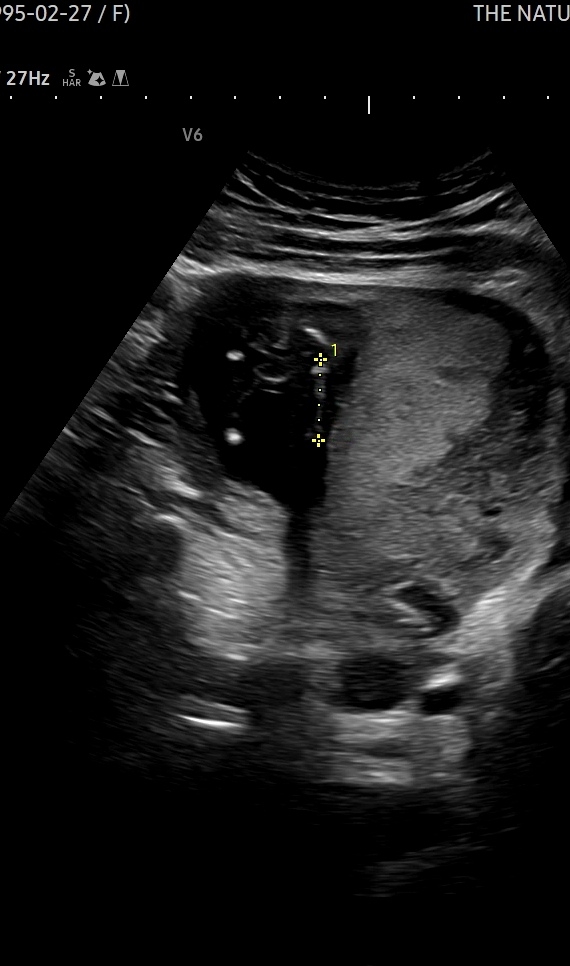

15주 3일인데 아들일까요?!

다른 아들 초음파 보면 대놓고 꼬추!!!!!! 가 있던데 이렇게 자꾸 애매하게 보여줘서ㅠㅠ 저 쩜 같은게 꼬추인지 뭔지... 모르겠어요ㅠㅠ 다리사이 초음파 인데 마미들 눈에는 어때보이나요..?